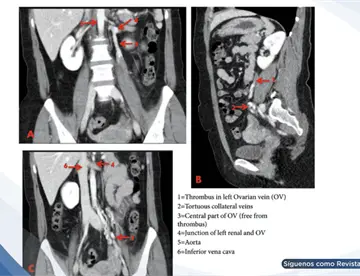

<content:encoded><![CDATA[<div><img src="https://blob.medicinaysaludpublica.com/images/2026/05/04/sacs-20--1089-300e16cb-focus-0-0-360-276.webp" alt="Hemorragia pulmonar por trombosis de vena cava simula sangrado digestivo en paciente en hemodiálisis " title="Hemorragia pulmonar por trombosis de vena cava simula sangrado digestivo en paciente en hemodiálisis "></div><p>Un hombre de 45 años con enfermedad renal crónica en hemodiálisis ingresó con aparente hematemesis e inestabilidad hemodinámica. Aunque el cuadro sugería un <strong><a href='https://medicinaysaludpublica.com/tags/sangrado/28213' target='_blank'>sangrado</a></strong> gastrointestinal superior, los estudios endoscópicos fueron inconclusos.&nbsp;</p>

<p>La tomografía torácica y la <strong><a href='https://medicinaysaludpublica.com/tags/broncoscopia/54407' target='_blank'>broncoscopia</a></strong> confirmaron una hemorragia pulmonar secundaria a trombosis de la vena cava superior, evidenciando un diagnóstico poco frecuente que puede imitar una emergencia digestiva.</p>

<p>En este contexto, la tomografía computarizada de tórax reveló un hallazgo clave: trombosis de la vena cava superior con abundante circulación colateral mediastínica. Además, se evidenciaron áreas de consolidación alveolar compatibles con hemorragia pulmonar y un derrame pleural derecho.</p>

<p>La <strong>broncoscopia</strong> fue determinante al identificar <strong>sangrado</strong> activo en el árbol bronquial derecho con presencia de coágulos adheridos, confirmando que la fuente del <strong>sangrado</strong> era respiratoria y no digestiva.</p>

<p>La trombosis de la vena cava superior genera aumento de la presión venosa proximal, lo que favorece la formación de vasos colaterales frágiles en el mediastino y árbol bronquial. Estos vasos pueden romperse y provocar hemorragia pulmonar.</p>

<p>En pacientes con enfermedad renal crónica, este riesgo se incrementa debido a la disfunción endotelial, el estado protrombótico y el uso repetido de accesos vasculares, factores que contribuyen al daño vascular y la formación de trombos.</p>

<p>Este caso, según Oscar Molina Lizama et al., resalta la importancia de considerar causas extraintestinales en pacientes con sospecha de <strong>sangrado</strong> digestivo cuando los hallazgos endoscópicos no son concluyentes. En particular, en pacientes en hemodiálisis con antecedentes de accesos venosos centrales, la trombosis de la vena cava superior debe incluirse dentro del diagnóstico diferencial.</p>

<p>La integración de estudios de imagen y <strong>broncoscopia</strong> resulta fundamental para identificar la fuente real del <strong>sangrado</strong>, evitar procedimientos innecesarios y dirigir un tratamiento oportuno y específico.</p>